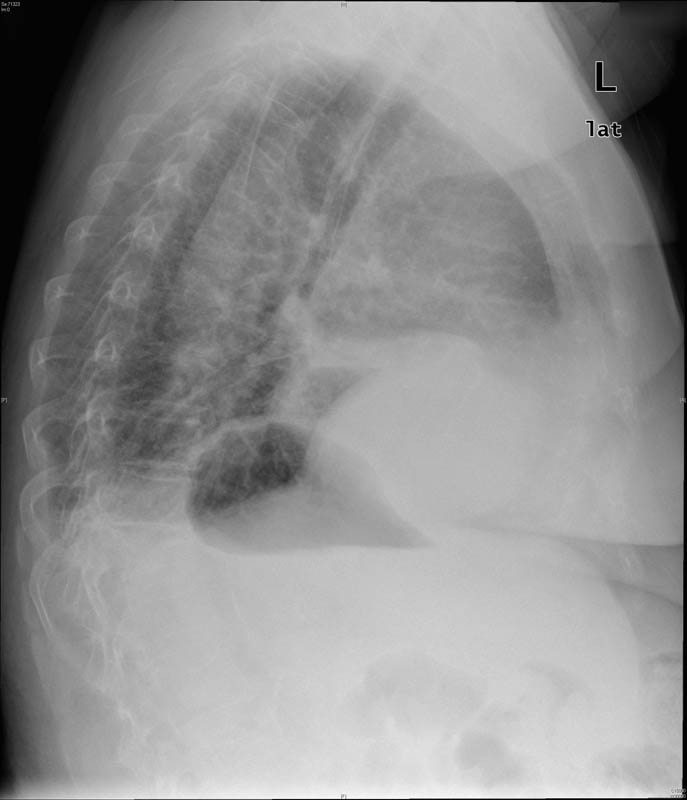

Atelectasia lóbulo medio.